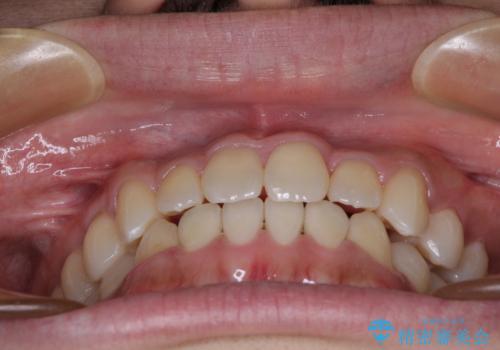

骨格的な左右差も顕著であったため、正中は合わず、上下前歯の一部が接触しない咬み合わせとなることが予想されましたが、正中はもともとのズレが小さかったことから、合わせることができました。

治療期間も10か月間という短期間で終了し、患者様には大変満足していただきました。